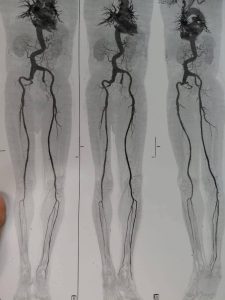

في إنجاز طبي جديد يُضاف إلى سلسلة النجاحات التي تحققها جامعة كفر الشيخ في المجال الطبي، نجح فريق جراحة الأوعية الدموية بمستشفى كفر الشيخ الجامعي في إجراء عملية جراحية متقدمة لإصلاح تمدد ضخم بالشريان الأورطي البطني والشرايين الحرقفية بالحوض باستخدام شريان صناعي متفرع، وذلك لأول مرة داخل محافظة كفر الشيخ.

الجدير بالذكر، أن العملية التي أُجريت بنجاح هي من العمليات الدقيقة والمعقدة جدًا، والمعروفة طبيًا باسم

Aorto bi-iliac bypass with re-anastmosis of IIA using a pantaloon graft for a huge AORTOILIAC aneurysm،

وقد خرجت الحالة بحمد الله بسلام وصحة تامة بعد أن تم التعامل مع التمدد الضخم بدقة وكفاءة عالية.